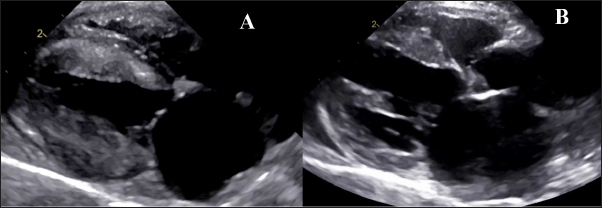

Fig. 1. Echocardiography. A- HCM group with hypertrophy of left ventricle walls, dilated left atrium, B— RCM-phenotype with hyperechogenic endomyocardium and loci in myocardial walls and dilated left atrium.

Animal echocardiography showed signs of typical morphology within the phenotypes. The HCM group had signs of ventricular wall hypertrophy (more than 6 mm, symmetrically or asymmetrically) as well as a dilated left atrium. The RCM group had a nonhypertrophied myocardium, hyperechogenic zones in the myocardial tissue, and a thickened endomyocardial layer, combined with dilated atria (Fig. 1).